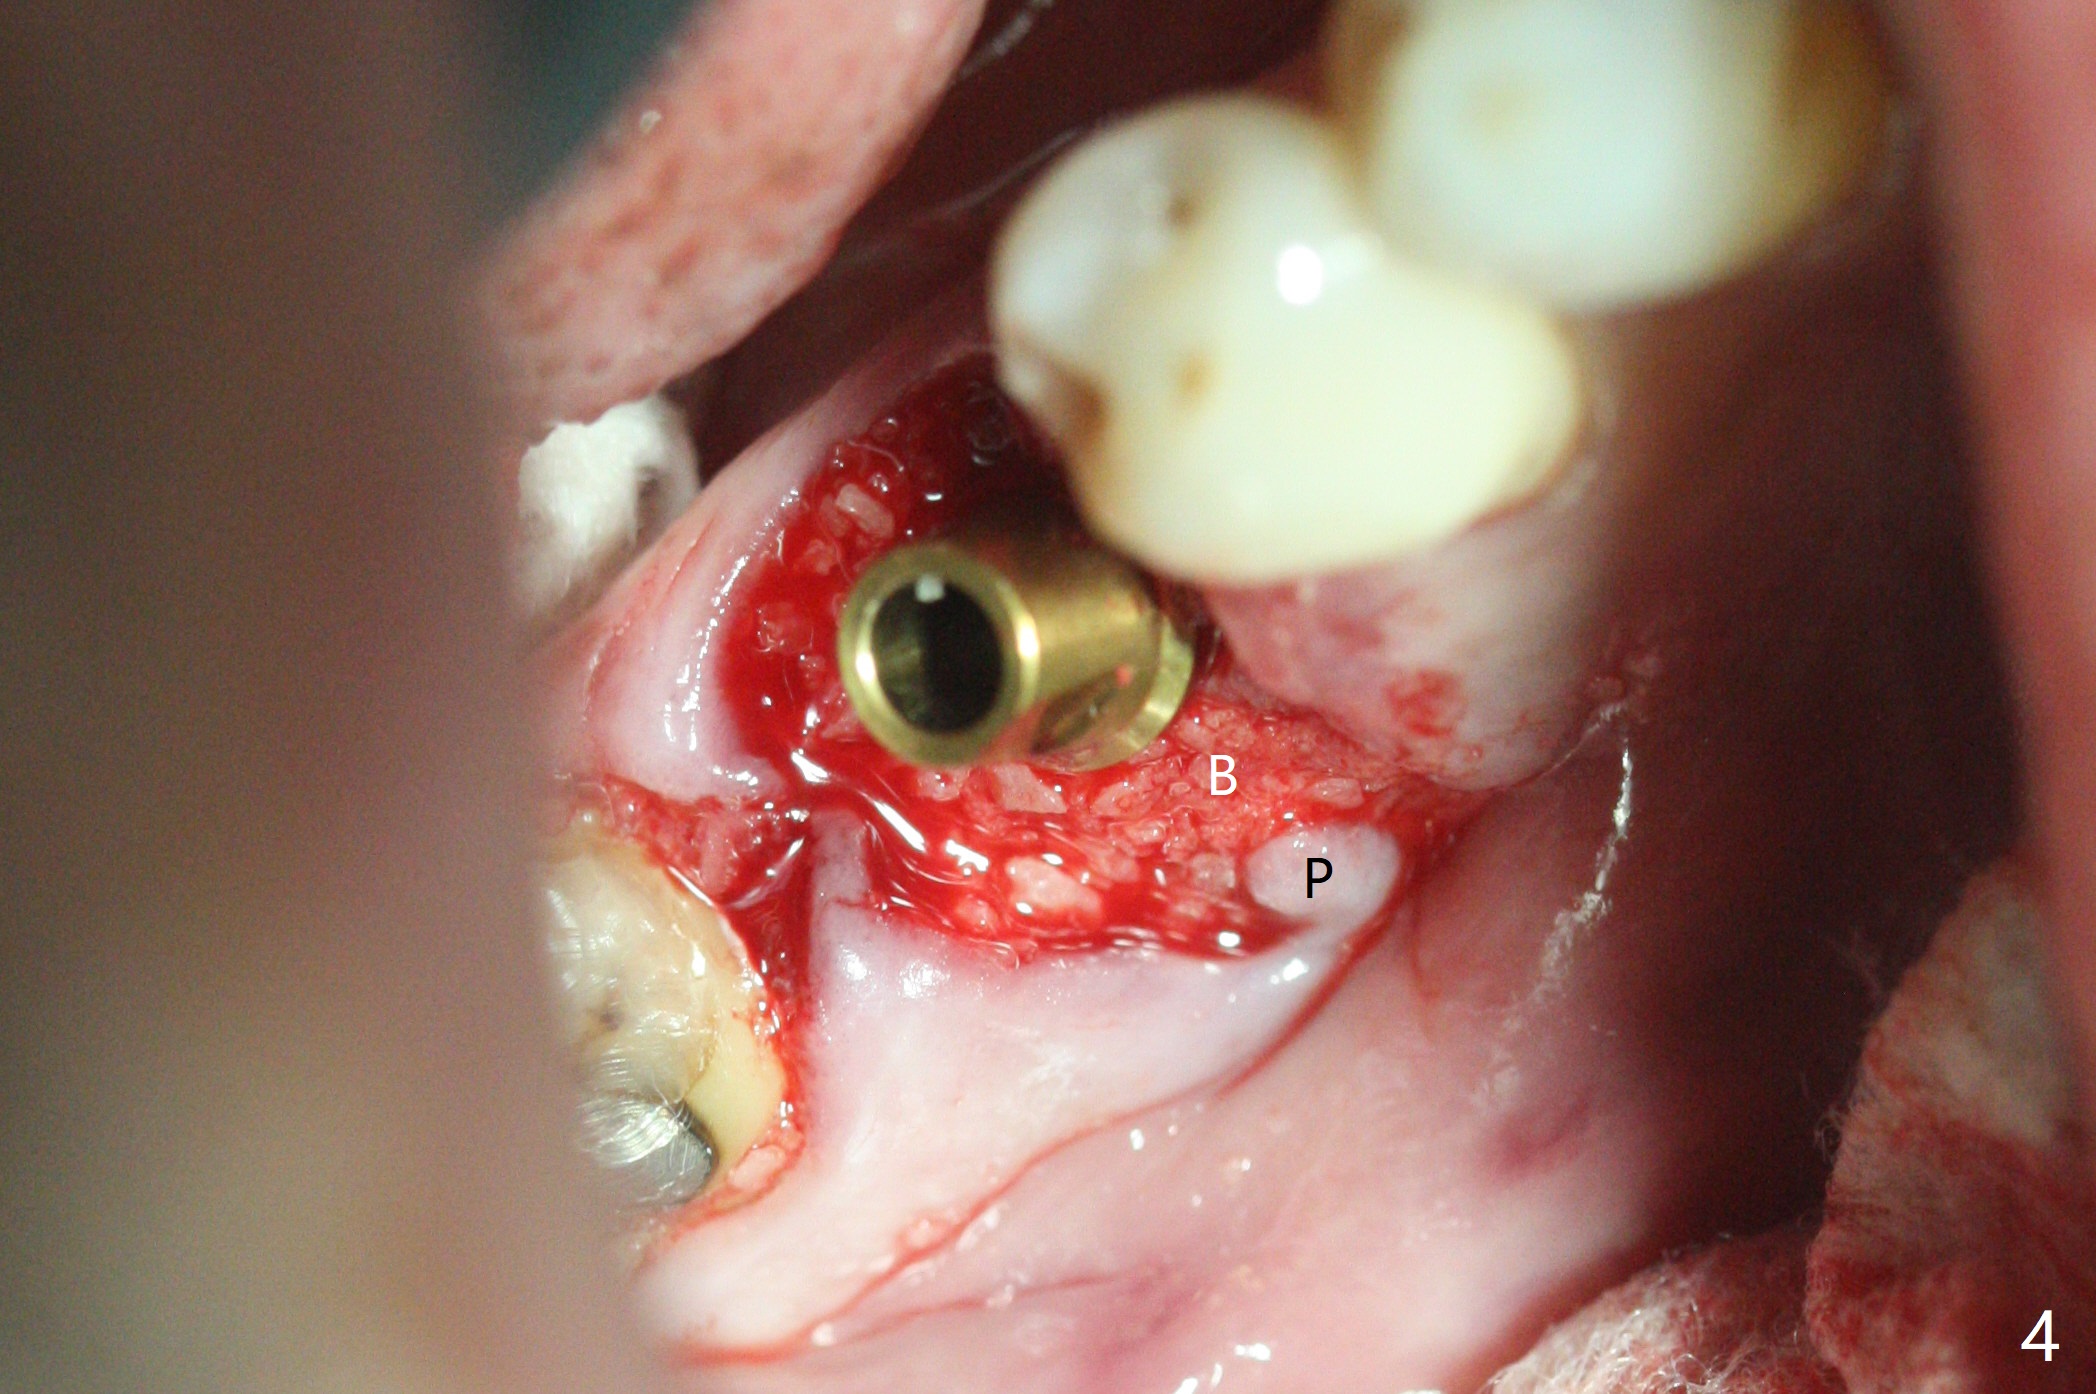

When the tooth #30 is extracted, the gingiva buccal to the septum (S in Fig.1,2 (P: papilla between the mesial and distal roots)) collapses. The latter is fixed with placement of a 4.5x11.5 mm implant (with guide), a 5.2x4(5) mm cemented abutment (Fig.3) and mixture of cortical bone (125μm – 850μm) and cortical/cancellous bone (.5-1 mm) with PRF (sticky bone, B in Fig.4-6). After placement of 2 pieces of PRF membrane over the bone graft, a temporary crown is fabricated to cover the buccal defect (Fig.7 T). Approximately 7.5 mm of the buccal threads are covered by the thick layer of bone graft (Fig.8 B). It is amazing to expect that the bone graft will turn into the buccal plate. It would be better if a narrower implant (4 instead of 4.5 mm) were placed more lingually or there were < 4 mm implant thread exposure (Fig.9). The gingiva reacts to the provisional nicely 7 days postop (Fig.10). The provisional will be removed for modification in 1 month. The patient complains of bad smell from the provisional 2 weeks postop. The provisional is removed. The distal socket (Fig.11 D) is healing, whereas the buccal bone graft (Fig.12 B) seems not have been vascularized. Pedicled flaps (I) should be transferred to cover the buccal bone graft. The margin of the provisional is polished, becomes short, and covered by periodontal dressing, which dislodges 2 days later. One week later, granulation tissue is forming apically with use of oral antibiotic and water jet (Fig.13 *). The bad smell reduces. The superficial loose bone graft changes colar and becomes detached 1 month 10 days postop. The temporary crown with the shortened buccal shelf is reseated for self cleansing or reapplication of PRF if needed (Fig.14).